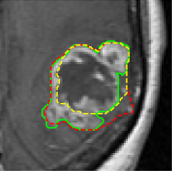

We argue that the sub-optimal paradigm of processing different abstractions within a single CNN pipeline can be remedied through the effective processing of information in a structured manner. Consequently, we devise strategies for disentangling the edge and texture information within a single training pipeline. Figure 2 illustrates how our proposed module, dubbed EG-CNN, can be paired with any existing CNN encoder-decoder to improve segmentation quality near intensity edges. We have applied our EG-CNN to the tasks of brain and liver tumor segmentation in medical images (Figure 3).

(1) Brain MR (2) Liver MR (3) Liver CT (4) Lung CT